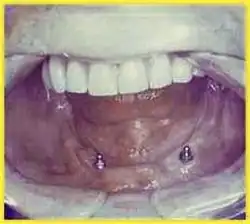

In der Zahnmedizin bietet die festsitzende Versorgung eine optimale Lösung für Patienten mit zahnlosem Kiefer. Abhängig von der Kieferform und dem Knochenangebot werden 4, 6 bis 8 Zahnimplantate eingesetzt. Wenn ein einzelner Zahn verloren geht, können Zahnimplantate eine empfohlene Lösung sein. Dadurch bleiben die gesunden Nachbarzähne von einem Beschliff und einer Überkronung verschont. Der Verlust der Backenzähne kann auch die Kaufunktion beeinträchtigen. Bei Verlust eines, mehrerer oder aller Zähne, wenn der Patient keinen herausnehmbaren Zahnersatz akzeptieren möchte, bevorzugt eine feste und dauerhafte Lösung, anstatt herausnehmbaren Zahnersatz zu tragen. Auf diesen Implantaten wird dann eine Brücke befestigt, die nicht mehr abgenommen werden muss.[3]

Klasse IIIb: Zahnloser Unterkiefer

- Für die Verankerung eines festsitzenden Zahnersatzes im zahnlosen Unterkiefer: 6 Implantate

- Für die Verankerung eines herausnehmbaren Zahnersatzes im zahnlosen Unterkiefer: 4 Implantate

Die Befestigung von Totalprothesen an Implantaten wird häufiger im zahnlosen Unterkiefer, als im zahnlosen Oberkiefer durchgeführt, weil Unterkieferprothesen auch häufiger Probleme bereiten. Dies liegt an der geringen Saugwirkung und der kleineren Auflagefläche einer Unterkieferprothese. Im Unterkiefer können zwei Implantate genügen, wobei die Kraftverteilung auf vier Implantate von Vorteil ist. Im Oberkiefer sollten aufgrund der weicheren Knochenstruktur mindestens vier Implantate eingesetzt werden.[66]

Die Implantate können über Stegverbindung (eventuell mit Friktionshilfen) miteinander verbunden werden. Das dient sowohl der Stabilisierung der Implantate als auch der besseren Prothesenverankerung. Bei einer guten Primärstabilität ist in bestimmten Fällen eine Sofortbelastung möglich.

Sind etwa 6 bis 8 Implantate vorhanden, kann eine Totalprothese allein auf diesen abgestützt werden. Eine Belastung der Kieferkämme entfällt dann, so dass kein Knochenabbau zu befürchten ist. Bei dieser Anzahl von Implantaten ist alternativ eine festsitzende Zahnersatzversorgung möglich. Ursprünglich als Sozialindikation gedacht, sind inzwischen verschraubte Brücken auf jeweils vier Implantaten im Ober- oder Unterkiefer möglich.[67][68] Dadurch können Kosten und Behandlungsdauer reduziert werden. Die Verweildauer ist bei dieser Art der Versorgung vergleichbar mit dem konventionellen Vorgehen.[69]